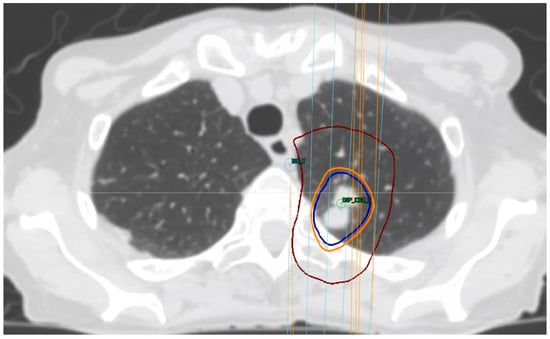

7. Treatment Volumes

8. Treatment Dose